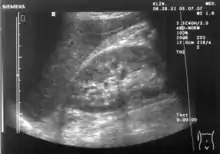

A normal ultrasonographic view of Morison's pouch. The bright line is the capsule of the kidney; there is no fluid present and hence no visible space.